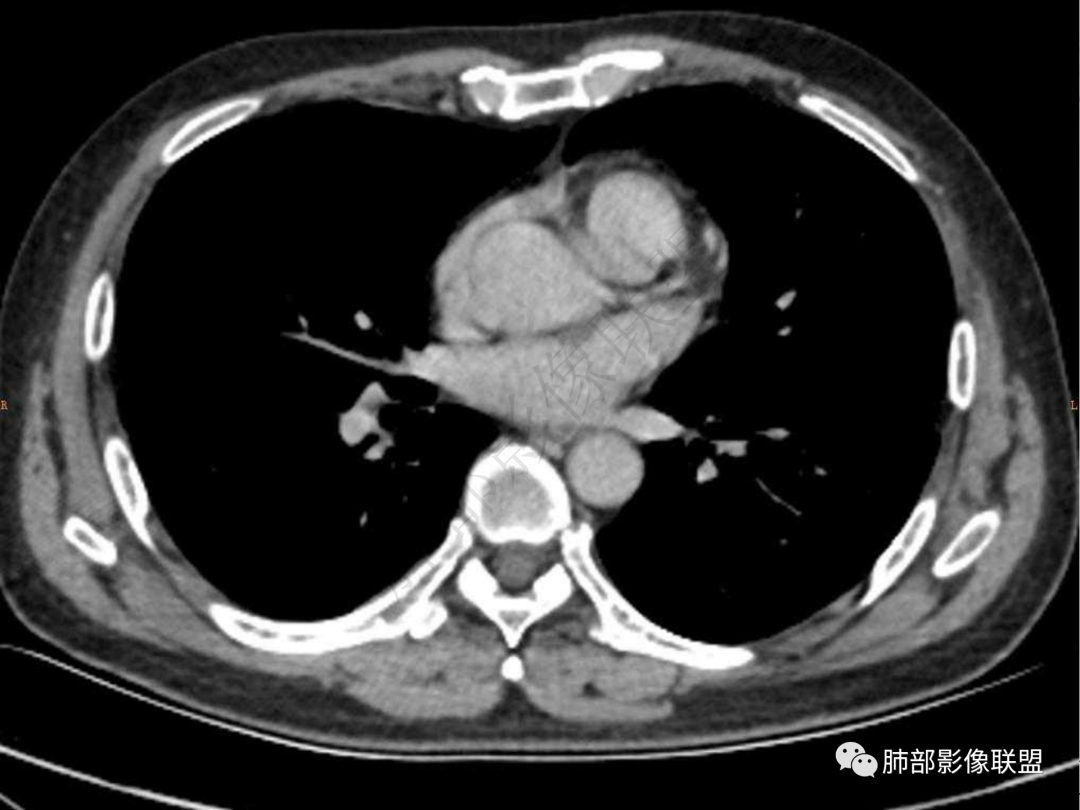

4.实性部分不均匀环形强化并显示一小范围低密度坏死区或空洞。较之肺窗,整体纵隔窗范围较小,提示病灶并不十分密实。抑或为不同时段图像。

5.双肺门及纵隔未见增大淋巴结。未见胸腔积液。